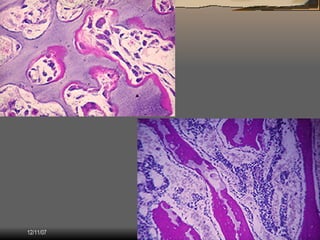

El documento describe los componentes y estructura del tejido óseo. El tejido óseo está compuesto de una matriz ósea mineralizada y células óseas. La matriz ósea contiene colágeno, proteínas y cristales de hidroxiapatita que le dan rigidez y resistencia. Las células óseas incluyen células madre, osteoblastos que secretan la matriz, y osteocitos encerrados en la matriz.